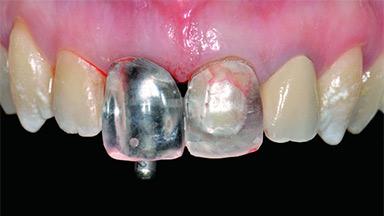

A 30-year-old patient presented at our clinic with a chief complaint of pain in her endodontically treated right maxillary central incisor (tooth 11) with a post-and-core and a fixed single crown. She had a very high lip line, a medium to thin soft-tissue phenotype, and a medium scalloped gingival contour. She also had high esthetic expectations because of her young age and beautiful smile. However, her expectations were realistic and she understood the risks of the treatment. At the initial clinical examination there was a slight mobility of tooth 11; no fistula was observed. The patient also had a single crown on the adjacent tooth 21. Both restorations were old and esthetically deficient. A digital periapical radiograph showed a very small periapical radiolucency, a thick intraradicular post, and no separation between root fragments.

Provisional Implant-Supported Prosthesis Prosthodontic margin > 3 mm apical to mucosal margin Prosthodontic margin > 3 mm apical to mucosal margin

Interim Prosthesis during Healing Fixed Fixed